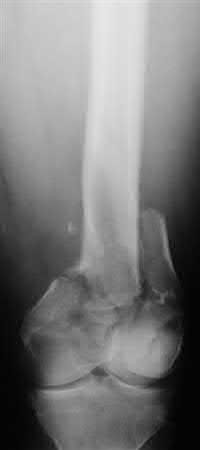

Which of the following fractures seen in Figures A through E would be amenable to fixation with a construct using tension band principles?

1) Figure A

2) Figure B

3) Figure C

4) Figure D

5) Figure E

In order for a fracture to be successfully treated with tension band principles the bone must be eccentrically loaded, the construct must be applied on the tensile side, and the opposite cortex must be able to withstand compressive

forces. Of the fractures seen in Figures A-E, the subtrochanteric fracture seen in Figure A best meets the criteria for stabilization according to tension band principles.

Illustration A demonstrates the principles of tension band fixation specifically applied to the femur. Within Illustration A, Figure C shows the correct application of a plate along the lateral cortex to resist tensile forces, along with incorrect application of the plate along the medial cortex (Figure D) or in a fracture pattern with an absent opposite cortex (Figure E). Illustration B shows an example of blade plate fixation of a subtrochanteric fracture.